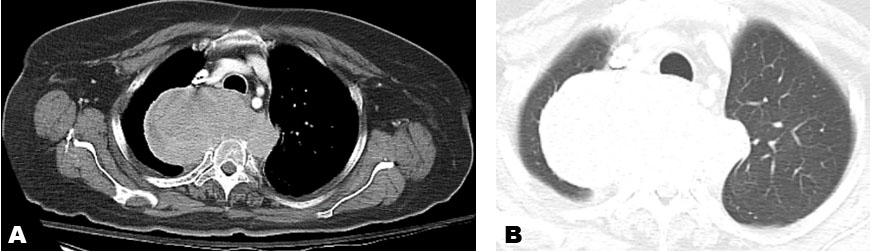

He remained without evidence of recurrent melanoma for the next three years, until routine surveillance positron emission tomography/computed tomography (PET/CT) demonstrated a new left lower lobe pulmonary nodule, the biopsy of which showed recurrent melanoma. He was started on nivolumab 240 mg every two weeks. During cycle 12 (his sixth month of treatment), he developed bilateral swollen flexor tendons to varying degrees of all fingers of his hands along with substantial accompanying tenderness and pain interfering with grasping objects, eating, and writing. He was able to perform activities of daily living (ADLs), such as feed and dress himself, though with significant discomfort. These symptoms rapidly developed over about one week. He could make a fist but could not relax it afterward due to severe pain in the palmar aspect of his hands. There was also erythema of the overlying skin (Figure 1). His fingers were otherwise not swollen, and he had no rheumatoid changes to the joints of his hands. Prior to onset of symptoms, he denied any trauma or medication changes. He had no medical history of auto-immune disorders, tendinopathies, osteoarthritis, soft tissue disorders, or chronic pain within his hands. He had no clinical evidence of infection. He had no other side effects other than chronic sequelae from his baseline COPD (for which he was not receiving oral or inhaled corticosteroids). His physical examination was normal. Considering the known association of nivolumab inducing soft tissue inflammation (and the patient having no similar past medical issues), nivolumab was held for two two-week cycles (about one month). During this period the swelling and pain in his hands greatly improved with slight residual pain in the flexor tendons and skin erythema (Figure 2), but he regained baseline function of his hands. Given the severity of his presenting symptoms, this irAE was considered Grade 3 of 5; i.e., affecting more than one finger or tendon; interfering with, but not preventing or limiting ADLs, and not requiring hospitalization or urgent intervention by Common Terminology for Adverse Events (CTCAE) Version 5.

Figure 1: Photo of the patient’s left hand and treatment-related tendon inflammation prior to delaying treatment with nivolumab.